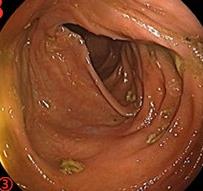

摘要:目的 探讨利那洛肽联合西甲硅油与复方聚乙二醇电解质散(PEG)对便秘患者肠道清洁效果的有效性和安全性。方法 采用前瞻性随机对照试验,通过单盲法,纳入2023年4月-2024年8月于该院消化内镜中心行结肠镜检查的便秘患者383例,随机分为常规组(128例)、实验A组(128例)和实验B组(127例)。常规组采用3 L PEG(Ⅰ)溶液,实验A组采用290 μg利那洛肽 + 2 L PEG溶液,实验B组采用290 μg利那洛肽 + 30 mL西甲硅油+2 L PEG溶液。比较3组患者的肠道准备效果[Boston肠道准备量表(BBPS)评分和去泡效果]、病变检出率、首次排便间隔时间、排便次数、盲肠插管成功率、进镜时间、退镜时间、不良反应发生率和重复检查意愿等。结果 3组患者BBPS评分比较,差异无统计学意义(P > 0.05);实验B组的去泡效果评分明显低于常规组和实验A组,差异均有统计学意义(P < 0.05);实验B组的病变总检出率和息肉检出率明显高于常规组和实验A组,差异均有统计学意义(P < 0.05);常规组的首次排便间隔时间明显长于实验A组和实验B组,差异均有统计学意义(P < 0.05);3组患者排便次数比较,差异无统计学意义(P > 0.05);3组患者盲肠插管成功率均为100.0%,进镜时间相当,差异均无统计学意义(P > 0.05);实验B组的退镜时间明显短于常规组和实验A组,差异均有统计学意义(P < 0.05);常规组腹胀腹痛发生率和不良反应总发生率明显高于实验A组和实验B组,差异均有统计学意义(P < 0.05);常规组重复检查意愿率明显低于实验A组和实验B组,差异均有统计学意义(P < 0.05)。结论 290 μg利那洛肽联合30 mL西甲硅油与2 L PEG溶液方案在便秘患者肠道准备上具有优势,较3 L PEG溶液和290 μg利那洛肽+2 L PEG溶液方案,可获得更好的肠道清洁效果,且安全性和患者重复检查意愿率高,可作为便秘患者肠道准备的推荐方案。